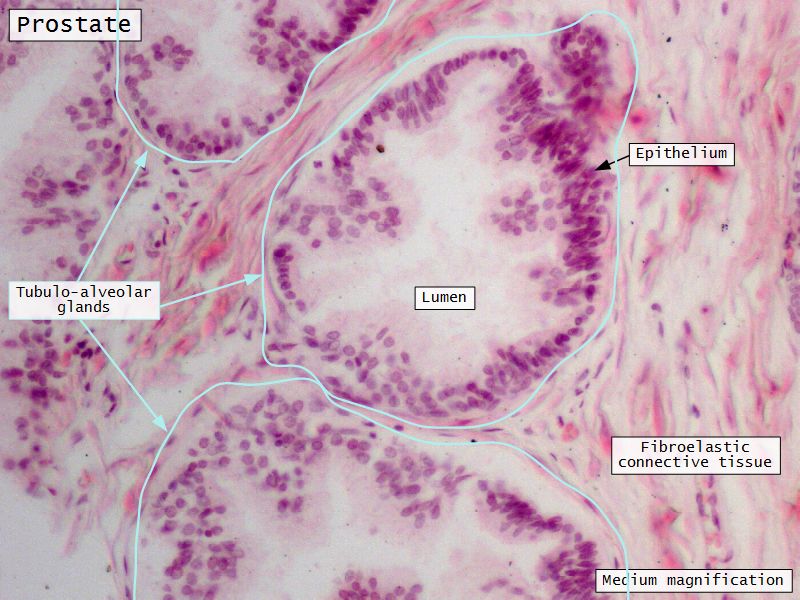

Prostate

Slide 80Prostate

- Surrounds urethra

- Largest accessory gland

- 30 - 50 branched tubuloalveolar glands

- Via excretory ducts

- Into urethra

Glands

- 3 concentric layers

- Around urethra

- Mucosal

- Submucosal

- Main

Capsule

- Fibroelastic capsule containing smooth muscle

- Divides into lobes

Concretions

- Sometimes in lumen

- Calcified

- Increase with age

Epithelium

- Simple columnar or

- Pseudostratified columnar

- Surrounded fibroelastic CT

- CT with rich vascular supply